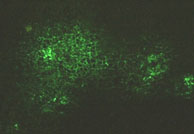

Self-delivering of 3’-fluorescent cationic oligonucleotide (19-mer, 5‘-conjugated to oligospermine) in HeLa cells. As control, the 3’-fluorescent 19-mer oligonucleotide used at the same concentration was not internalized by the cells (Nothisen et al., 2009).

Improved diffusion of fluorescent SIRNAPLUS® in subcutaneous melanoma B16-F10 tumors after intratumoral injection of cationic siRNAs.